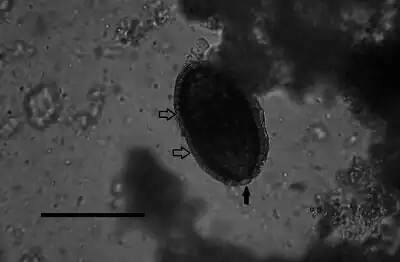

Adult worms take the shape of a slender nematode, with the anterior part of the body narrow and the posterior part gradually swelling.[5] The females measure about 53–78mm x 0.11–0.20mm, but the males are approximately 24–37mm x 0.07–0.10mm.[5] The adult worms are rarely seen intact, as they mature and die in the parenchyma of the liver.[6] The adult females lay eggs that are about 48-66μm x 28-36μm.[5] The shell of the eggs is striated with shallow polar prominences at either end. Numerous mini-pores can be seen in the outer shell as well. Unembryonated eggs may be ingested by a carnivore, in which case they are harmless and pass out in the feces. Eggs will embryonate in the environment, where they require air and damp soil to become infective. Under optimal conditions this takes about 30 days. Larvae are juvenile versions of the adult worm.[1]

Diagnosis is made by finding eggs or adults of C. hepatica in liver tissue from biopsy or Necropsy samples.[1] The encapsulated eggs and adults may appear as white nodules which measure 2–3mm in diameter on the surface and interior of the liver at autopsy.[17] Key identification features of this parasite are a striated shell and shallow polar prominences of the egg and a narrowing at anterior end and gradual swelling at posterior end of the adult worm. Identification of C. hepatica eggs in the stool does not result from infection of the human host, but from ingestion by that host of livers from infected animals, the eggs will then pass out harmlessly in the feces.[1] Most cases have been determined after death because clinical symptoms resemble those of numerous liver disorders.[1]